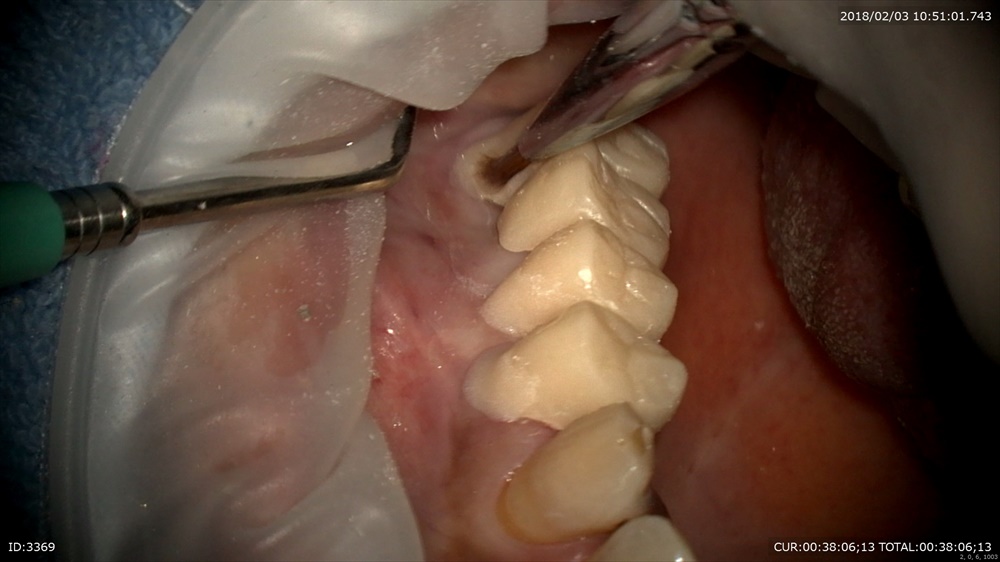

歯周病治療が終わり次のステップ。銀歯のブリッジが入っています。一見なにもない。症状もありません。歯科ドックでこの下に大きな虫歯が発見されました。本当でしょうか?のりが挟まっている。ということはここに隙間がある。=ここから細菌の進入が!!

わーーー

ほら。歯科ドック受けてよかったですね。

手前もぼろぼろ。でも救えます。まずは即席で仮歯を。ここが大切。むき出しになった歯は感染します。